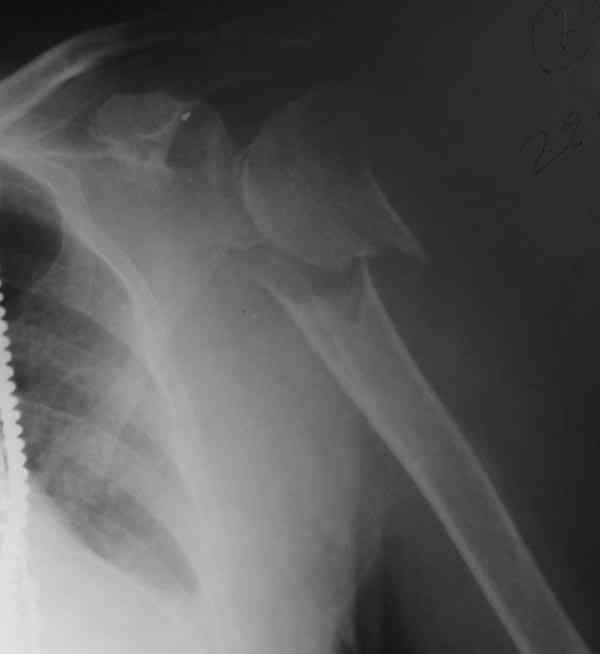

The fracture is completely displaced in the axial view. It is probably possible to align it with the patient in the vertical position, i.e. sitting or standing. However, I would use a locking plate for the tremendous pain relief it offers.

I am attaching the radiographs of the mother of a doctor. She has chronic renal failure for >10 years, diabetes mellitus and coronary artery disease. Age 62. She was offered the options of non-surgical management in a sling and surgery with a locking plate. She was given Tramadol for pain relief. Five days after injury, patient requested surgery, because of pain, inability to move without pain.

The reduction is not perfect. The patient is very small made, and it was difficult to bring the plate proximally without impingement in abduction.